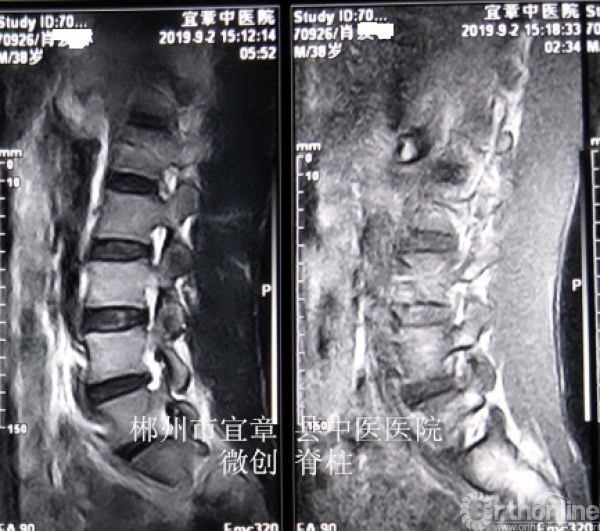

MRI、CT影像学表现:

术后复查MRI示突出物已经取出,患者感觉效果杠杠滴,很满意。